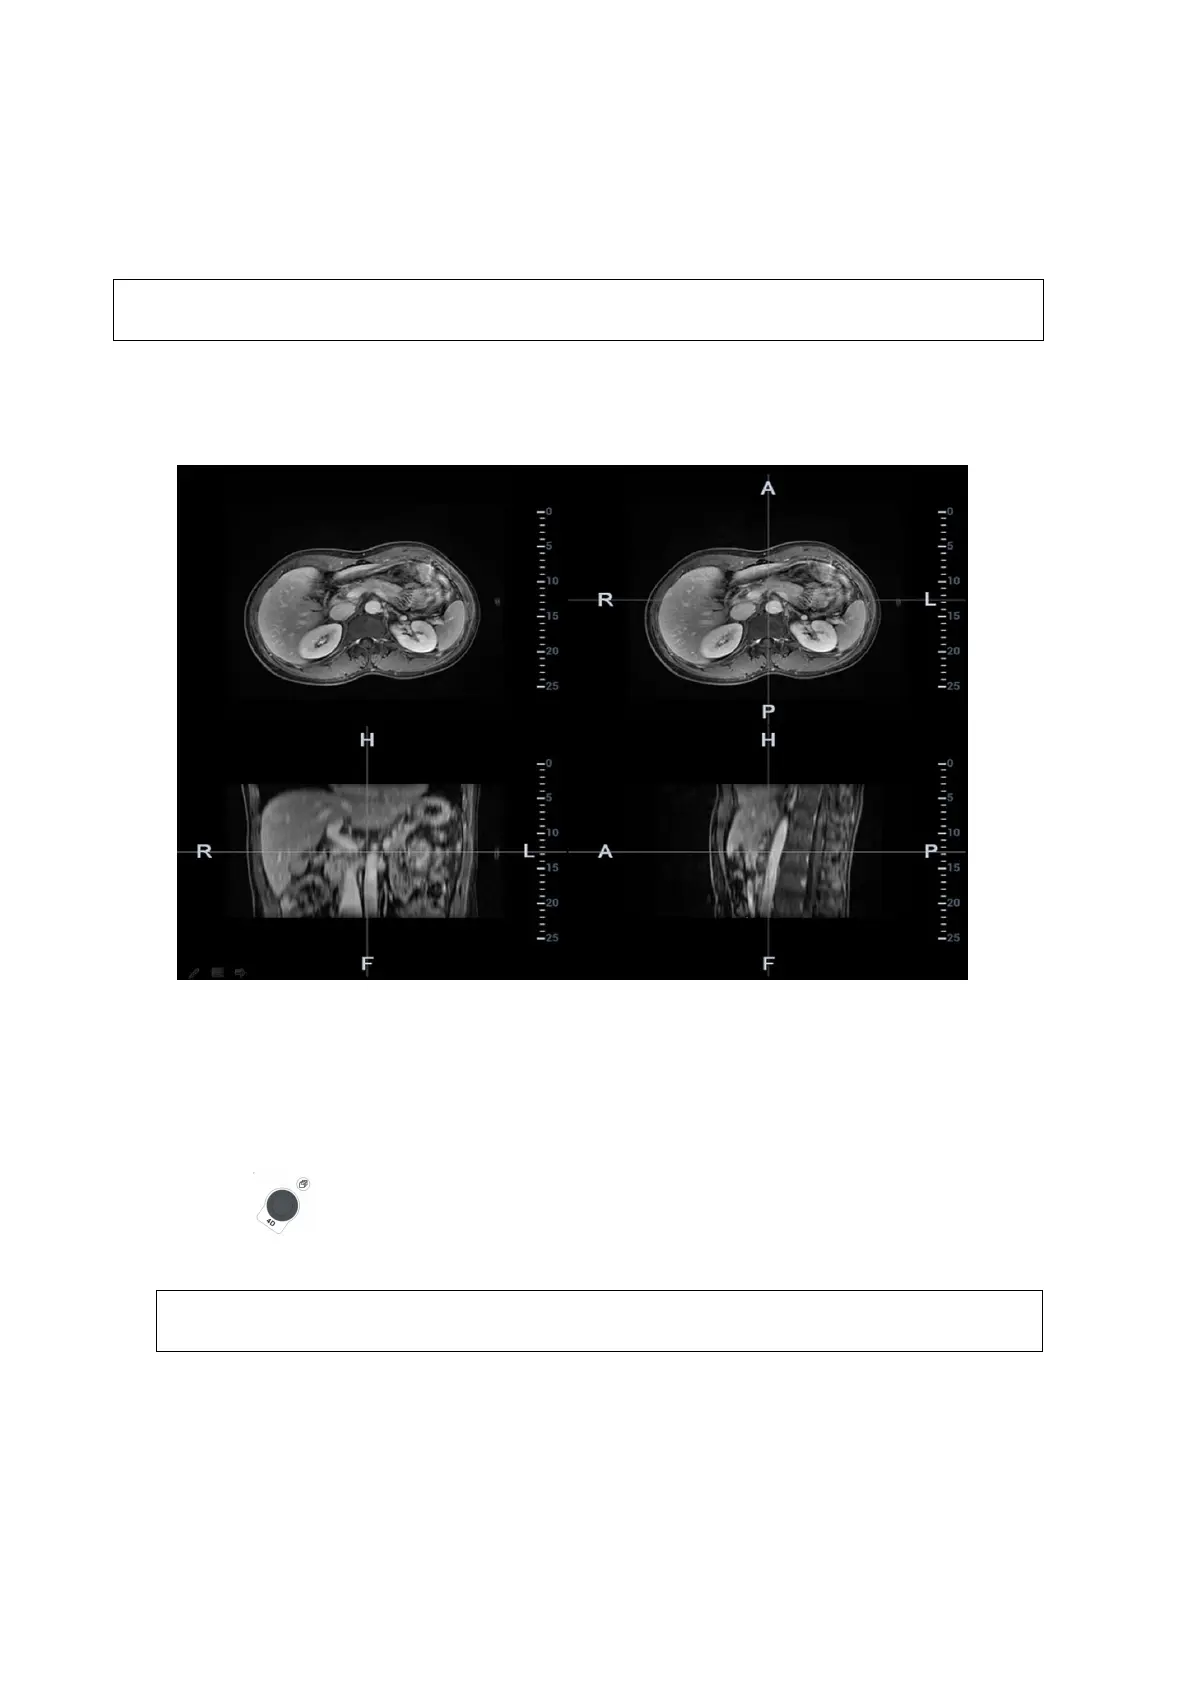

Mark tumor position, lesion position on CT/MR image. Be sure of the lesion appearing on US and

CT/MR image at the same time after the registration is completed.

1. Tap [Mark on CT/MR] to enter the page. Select [Add Marks][Display Marks] to activate the

mark.

Tap [Axial]/[Coronal]/[Sagittal] to toggle the top-left reference plane.

2. Press <Cursor> to show the cursor. Mark on the axial plane (top-right)/coronal plane (bottom-

left)/sagittal plane (bottom-right). The procedures to make marks are given below: